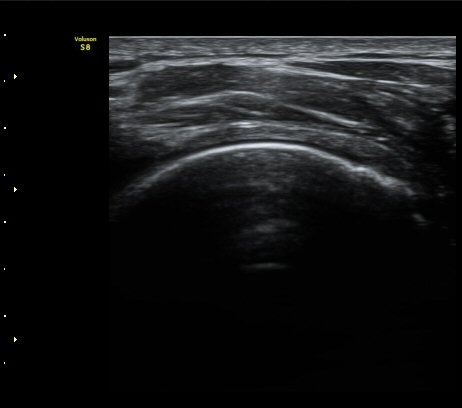

±Ø»ó°Ç Á¾´Ü¸é°Ë»ç¿¡¼­ ±Ø»ó°Ç ³»Ãø°ú ¿ÜÃø¿¡¼­ ÀüÃþÆÄ¿­ ¼Ò°ßÀ» º¸ÀÓ(½ÃÁø 1, 2).